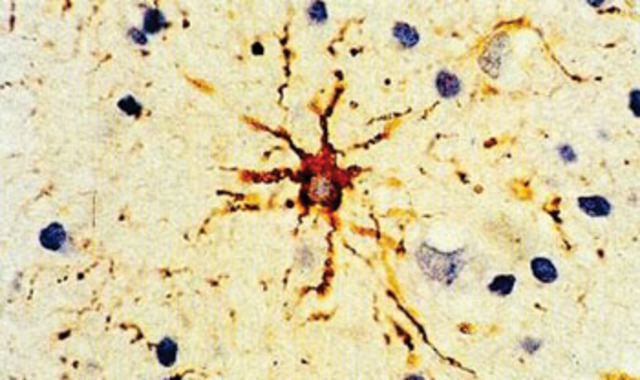

sistema nervioso SN

Es un conjunto de organos y una red de tejidos nerviosos cuya unidad básica son las neuronas.

Santiago Ramón y Cajal

Desarrollo del microscopio y de las técnicas de fijación y tinción de los tejidos

CAJAL

formuló la doctrina neuronal -el sistema nervioso está formado por células independientes, las neuronas, que contactan entre sí en lugares específicos- y construyó un gran cuerpo de doctrina neuroanatomical.